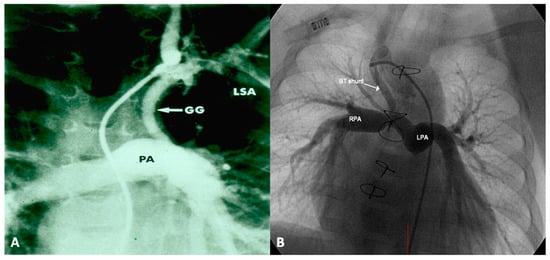

If the predominant obstruction is at the pulmonary valve level, though uncommon, balloon pulmonary valvuloplasty [12,13] to increase the pulmonary blood flow may be performed; balloon pulmonary valvuloplasty apart from increasing pulmonary blood flow, promotes growth and development of the pulmonary artery (Figure 2) and left ventricle so that a total surgical corrective procedure could be performed safely at a later time [12,13,14,15,16].

In premature babies two different palliative procedures were used as a bridge to total correction later. Balloon pulmonary valvuloplasty has been used in premature babies with TOF and significant arterial desaturaion as a bridge to total correction [17]. Similarly, deployment of a stent in RV outflow tract (Figure 3) may be used to promote growth of the pulmonary arteries and facilitate complete surgical correction at a later time [18].

In patients with low O2 saturations and inadequate pulmonary blood flow, PGE1 infusion to open the ductus and/or an aortopulmonary shunt to augment the pulmonary blood flow may be required. In patients with adequate pulmonary blood flow with O2 saturations between 70% and 90% no immediate intervention is necessary. In patients with CHF, anti-congestive measures as detailed in Part 1 [1] should be instituted. Sometimes trans-catheter occlusion of a collateral vessel causing excessive pulmonary blood flow may needed (Figure 4) after ensuring that dual supply to the lung segments is present.

Once the baby is stabilized, cardiac catheterization and selective cine-angiography is performed to delineate the PA anatomy (atresia, degree of PA hypoplasia, confluence or lack of it), sources of pulmonary blood flow and degree of connections between central PAs and MAPCAs, and presence of dual supply to pulmonary arterial segments. If the native PAs are of adequate size (>50% of normal) and if the estimated RV systolic pressure following operation is less the 70% of LV systolic pressure, total correction is indicated. The latter assessments may be made by the use of McGoon ratio or Nakata index [33].

If the infant’s anatomy is not suitable for total surgical correction, staged reconstruction is contemplated. RV outflow tract is reconstructed with either a trans-annular patch or RV-to-PA conduit (usually a homograft) in an attempt to encourage growth of the native PAs. Such procedures also provide anterograde catheter access so that a more precise delineation of the pulmonary arterial tree can be undertaken and balloon angioplasty or stenting of PAs, as necessary, can be performed. Such interventions decrease RV pressures, augment flow to distal PAs and reduce ventilation/perfusion mismatch. Once adequate pulmonary blood flow is established the remaining aortopulmonary collaterals could be occluded by trans-catheter methodology, and the VSD is closed surgically.